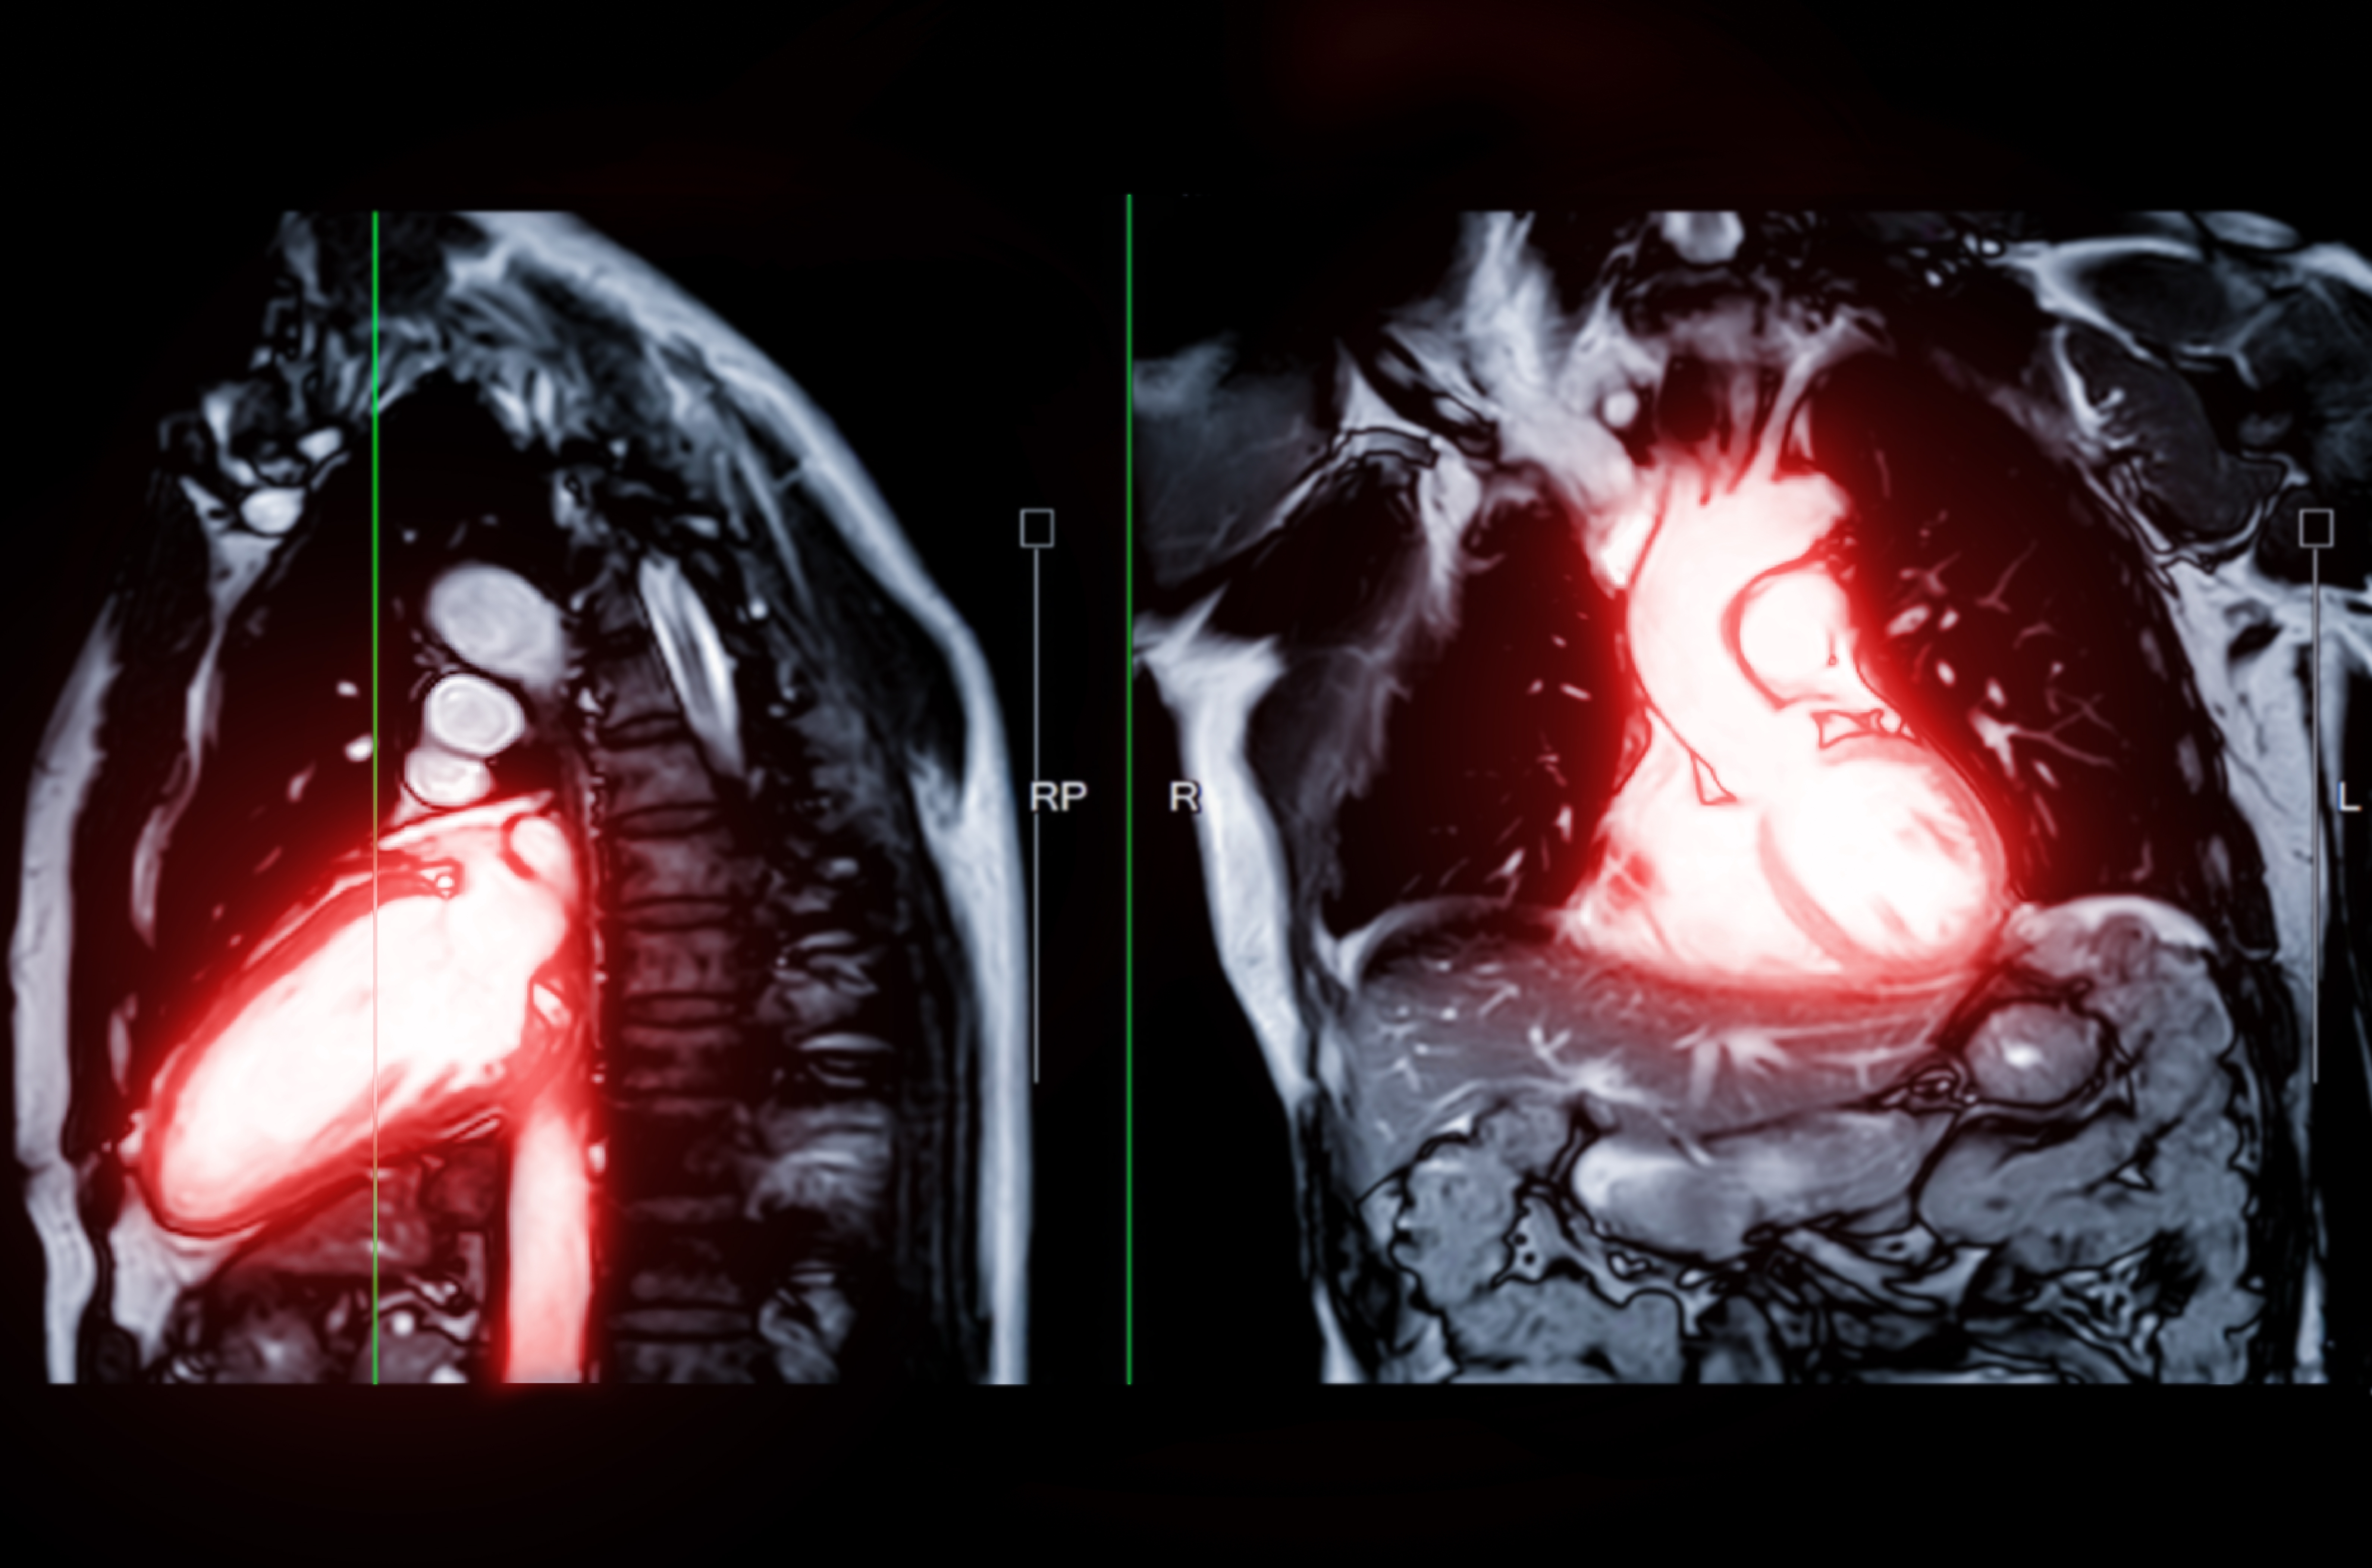

L'imagerie cardiovasculaire est une sous-spécialité de la radiologie qui permet de

visualiser l'état circulatoire de l'appareil cardio-vasculaire à des fins diagnostiques,

thérapeutiques ou de recherche. Elle permet d’analyser votre cœur et l'anatomie

environnante.

Elle est utilisée pour diagnostiquer et gérer les maladies cardiaques, déterminer si

une crise cardiaque s’est produite et l’étendue des dégâts, trouver la cause de

certains symptômes tels que des douleurs thoraciques et un essoufflement, surveiller

le cœur pour évaluer si les traitements fonctionnent.

Les examens comprennent les radiographies, l’échographie, l’IRM et le scanner.